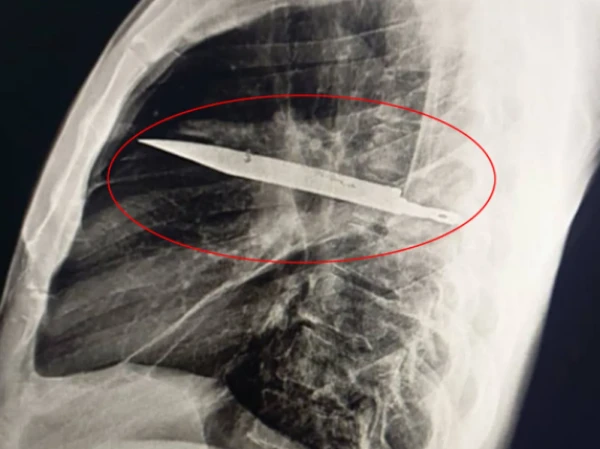

ڈاکٹروں نے ایکس رے کیا تو سینے کے اندر ایک بڑا چاقو موجود پایا، جو شاید اس کے دائیں کندھے کی ہڈی میں داخل تھا لیکن حیرت انگیز طور پر کسی اہم اعضا کو نہیں چھیڑا تھا۔

مریض نے بتایاکہ تقریباً آٹھ سال پہلے ایک پرتشدد جھگڑے کے دوران اسے چوٹیں آئیں۔ اس وقت زخموں کا صرف ابتدائی علاج ہوا مگر چونکہ کوئی شدید تکلیف نہ ہوئی، اس لیے ریڈیولوجی ایکسرے نہیں کروایا گیا۔

آپریشن کے ذریعے چاقو کو احتیاط سے نکالا گیا اور ساتھ ہی مردہ بافتوں اور پیپ کی صفائی بھی کی گئی۔ مریض نے 24 گھنٹے آئی سی یو میں گزارے پھر عمومی وارڈ میں 10 دن داخل رہا۔